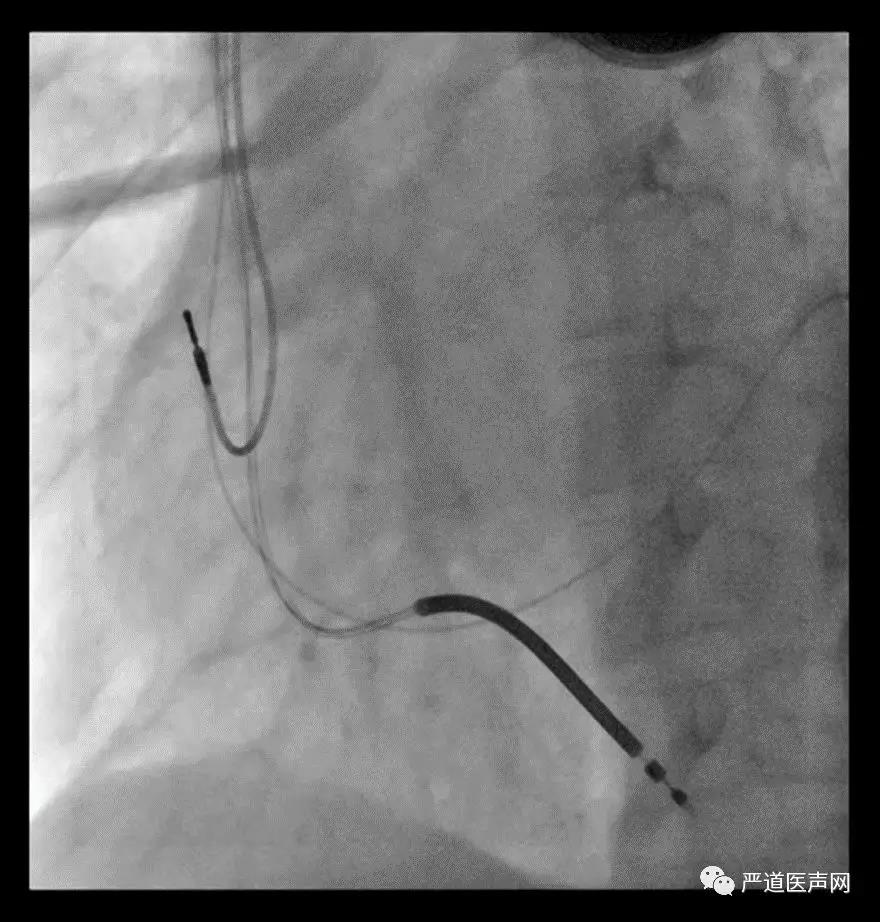

52岁女性患者,因劳力性气促2年,加重3天入院。查体BP 87/53mmHg,双肺可闻及湿罗音,心界向左扩大,心率120次/分。心电图示心房扑动,LBBB(QRS时间0.15s),室性早搏。心脏彩超示Lvd 59mm,EF 20%。诊断为扩心病,房扑,全心衰,心功能III-IV级。符合CRT-D适应证。手术要点:尝试多种方法寻找冠状窦口失败,考虑冠状窦畸形,从股静脉顺利置入冠状窦电极导管,保留下肢冠状静脉窦的电极,指引导丝至下腔静脉,电极顺利进入冠状窦。

23.jpg

24.jpg

25.jpg

术中影像